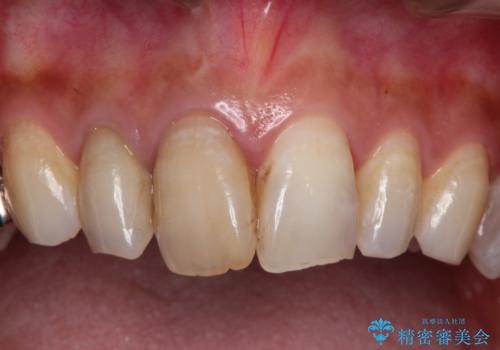

歯並びの改善とインプラントでのかみ合わせの回復 インプラント・セラミック・矯正全顎治療

- 歯医者が怖くて悪い歯をそのままにしてしまった、悪いところを治したいとのことで来院されました。

虫歯の歯や、歯を抜いてしまったところをそのまま放置していたことにより、歯並びも悪くなっていました。

矯正をはじめ、根の治療・インプラント・セラミックによる全体治療を提案させていただき、治療をしていくこととなりました。